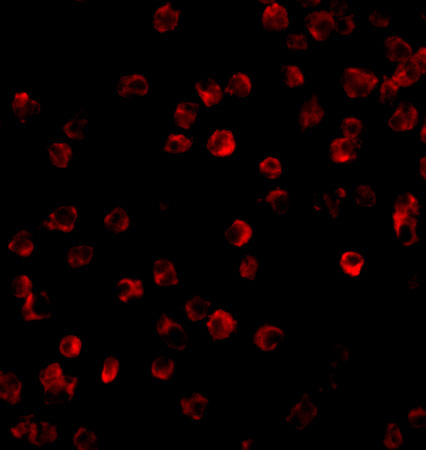

Predominantly expressed in B-lymphocytes.

Cytoplasm. Cell membrane; Peripheral membrane protein. Nucleus. In steady state, BTK is predominantly cytosolic. Following B-cell receptor (BCR) engagement by antigen, translocates to the plasma membrane through its PH domain. Plasma membrane localization is a critical step in the activation of BTK. A fraction of BTK also shuttles between the nucleus and the cytoplasm, and nuclear export is mediated by the nuclear export receptor CRM1.